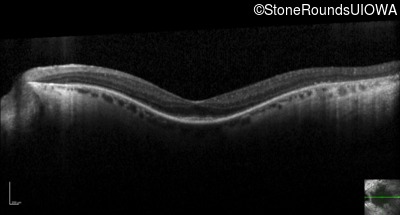

Optical Coherence Tomography - Left - 20/50

Exemplar / OCT Stack

OCT Stack